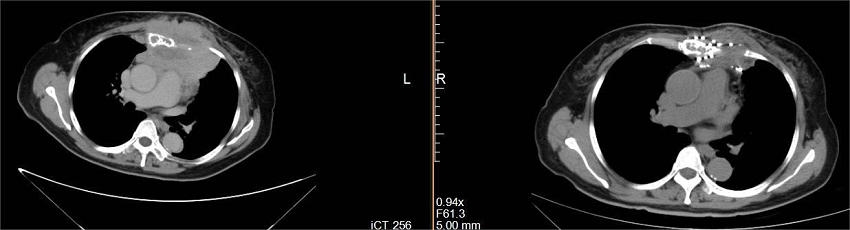

半年前65岁的祁阿姨体检查胸部CT发现前纵隔占位,侵及胸骨及部分肋骨,与纵隔血管关系密切,伴有胸骨疼痛。

入住郑州大学五附院肿瘤内科,经穿刺活检确诊为乳腺癌多发转移(前纵隔、前胸壁、骨、心包、心脏),经医院多学科会诊,专家组制定了治疗计划:1、患者多发转移,已失去手术时机;2、患者肿瘤负荷大,可行CT引导下经皮穿刺前纵隔、胸壁转移癌氩氦刀冷冻消融术+碘-125放射性粒子植入术联合全身化疗。

乳腺癌纵隔及胸壁转移氩氦刀冷冻消融联合放射性粒子植入治疗前、中、治疗后对比

经过冷冻消融、碘-125放射性粒子植入术,并4个周期全身化疗后,病灶明显缩小。祁阿姨原本确诊时沉重心终于如释负重,阿姨久违的笑容再次出现了。